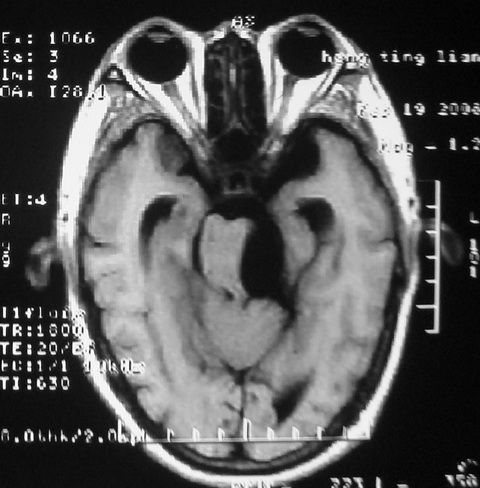

m,72,头疼,头晕两年,伴视力模糊三月,饮食呛咳两天。pe:颈部抵抗,左眼突出,左眼瞳孔约3mm,对光反射消失,双眼失明,伸舌困难,双肺呼吸音粗,心率110次/分,左上肢肌力i级,左下肢屈曲,肌张力高。现有08年2月19mri平扫及10年2月8日mri增强请会诊。ct病灶呈低密度伴散在点、片状等密度区,无明确钙化(无ct片资料可供上传)。[

脑外肿瘤,表皮样囊肿可能性大。

脑外肿瘤,囊实性,环状不规则强化,内听道扩大,考虑神经源性肿瘤

脑外肿瘤,病灶呈匍匐蔓延,表皮样囊肿可能性大。

脑外肿瘤,病灶呈匍匐蔓延,表皮样囊肿可能性大。支持!